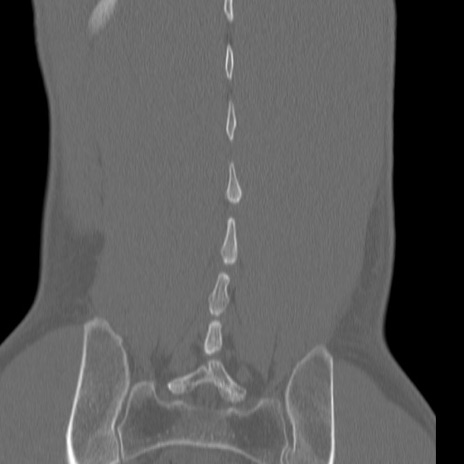

症例3 腰椎CT(冠状断像)

腰椎CT

3D再構成